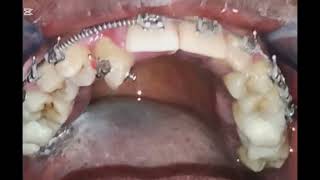

Self Ligating Braces| The Journey Begins\ Case Life@Sudan Crowding Open Bite #braces #dentist #smile